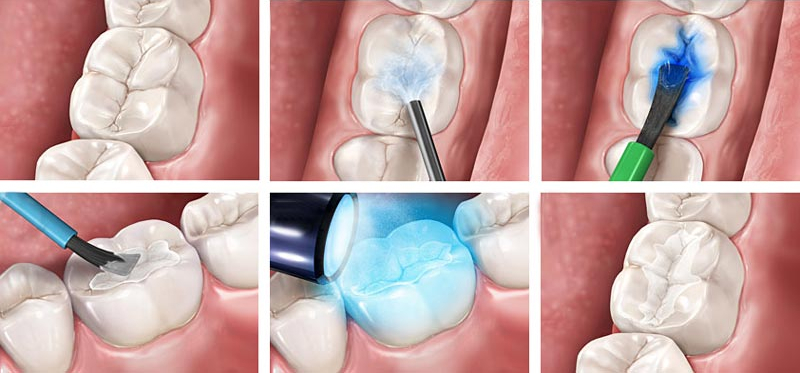

Реплантация зуба: Этапы и особенности операции